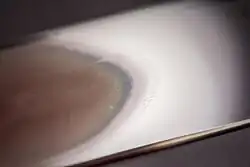

Closeups of the feathered edge of blood smears. The pale middle band of the gradient is the monolayer.